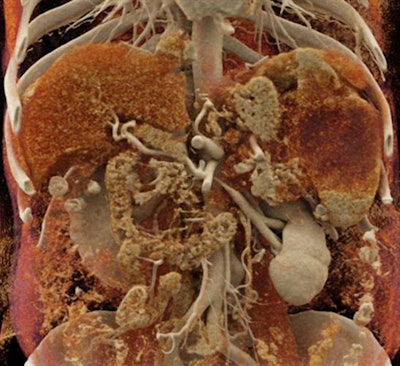

Minnies 2019 winner: Cinematic rendering of an abdominal scan, Dr. Elliot Fishman et al.

A prolific Minnies winner since the awards began in 2000, Dr. Elliot Fishman of Johns Hopkins University will need to make room on the shelf for two more trophies this year. In addition to the 2019 Minnie for Best Radiology Image, Fishman was also voted in as this year's winner of Best Educational Mobile App (see above) and has now received a record 10 Minnies.

This year's winning image shows many different organs and the relationship of the normal and abnormal structures together -- packing a lot of information into one image, said Fishman, who has worked with cinematic rendering technology since 2016.

Cinematic rendering of an abdominal CT scan. Image courtesy of Dr. Elliot Fishman.

Cinematic rendering of an abdominal CT scan. Image courtesy of Dr. Elliot Fishman."We've been volume rendering for 35 years, but I think cinematic [rendering] takes volume rendering to a different level," he said. "You really do feel like you're seeing the pathology from inside of the patient, so I think that's why people like it."